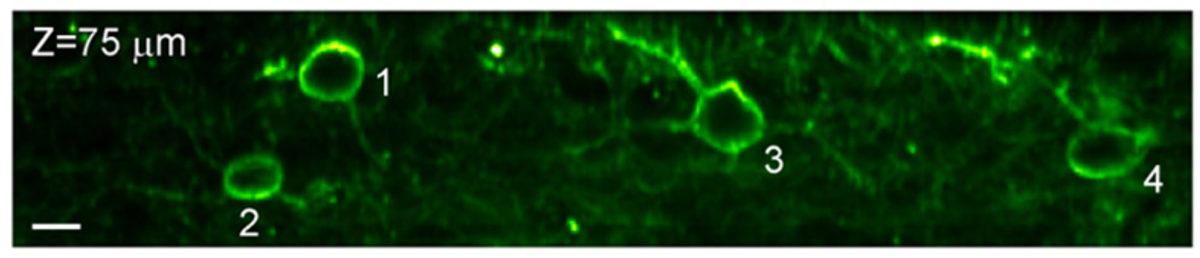

Yeni görüntüleme tekniği, iki boyutlu bir floresan mikroskopisini ve optik lazer taramayı, fare beyninin neokorteksinden iki boyutlu bir dilimini saniyede 3.000 defa görüntüleyebilen son teknoloji bir mikroskopta birleştiriyor. Bu teknoloji beyin devrelerindeki elektrik sinyallerini izlemek için yeterince hızlı.

Na Ji ve Berkeley’den bilim insanları, farenin beynindeki kalsiyum sinyallerini görüntülemeyi baz alarak yeni tekniği geliştirdiler. Araştırmacılara beyindeki kalsiyum konsantrasyonları, sinyalleri iletilirken voltaj değişikliklerine neden olurlar.

Ji ve meslektaşları, belirli hücre tiplerine sabitlenebilen ve ortam değiştiğinde floresan olabilen problar sayesinde beyni görüntülemeyi başarabildiler. Araştırmacılar, nöronlardaki voltaj değişikliklerini izlemek için Stanford Üniversitesi’nden Michael Lin tarafından geliştirilen bir sensörü kullandılar.